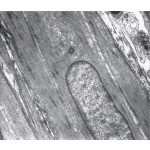

Electron Micrograph of Smooth Muscle In Longitudinal Section